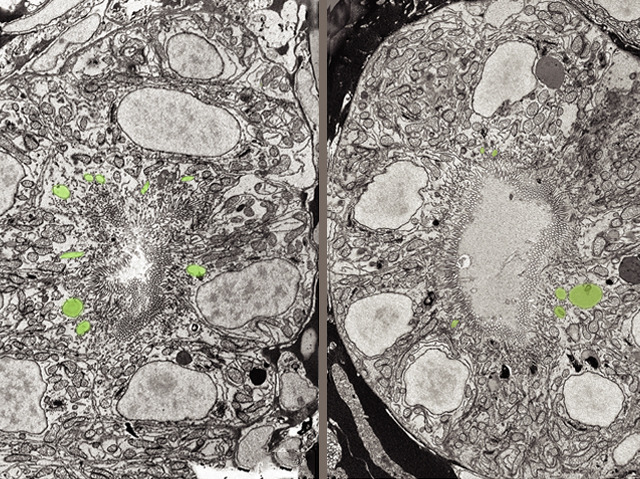

At just three days old, a zebrafish embryo is busy building its internal organs. These images – taken using a high-powered electron microscope – show two of the multitude of tiny tubes within a growing fish kidney, made up of tightly packed cells clustered round a central hole. Falsely-coloured green are the endosomes, small packets of molecules that are important for helping cells to function properly. On the left is a healthy tube, but the one on the right comes from a fish with a faulty version of a gene called OCRL1. The endosomes are abnormal and the hole in the tube is much larger, causing kidney problems later in life. Faults in human OCRL1 also cause kidney defects, so figuring out what the gene is doing in fish will shed light on how things go wrong in our own species, pointing towards new treatments for sufferers.